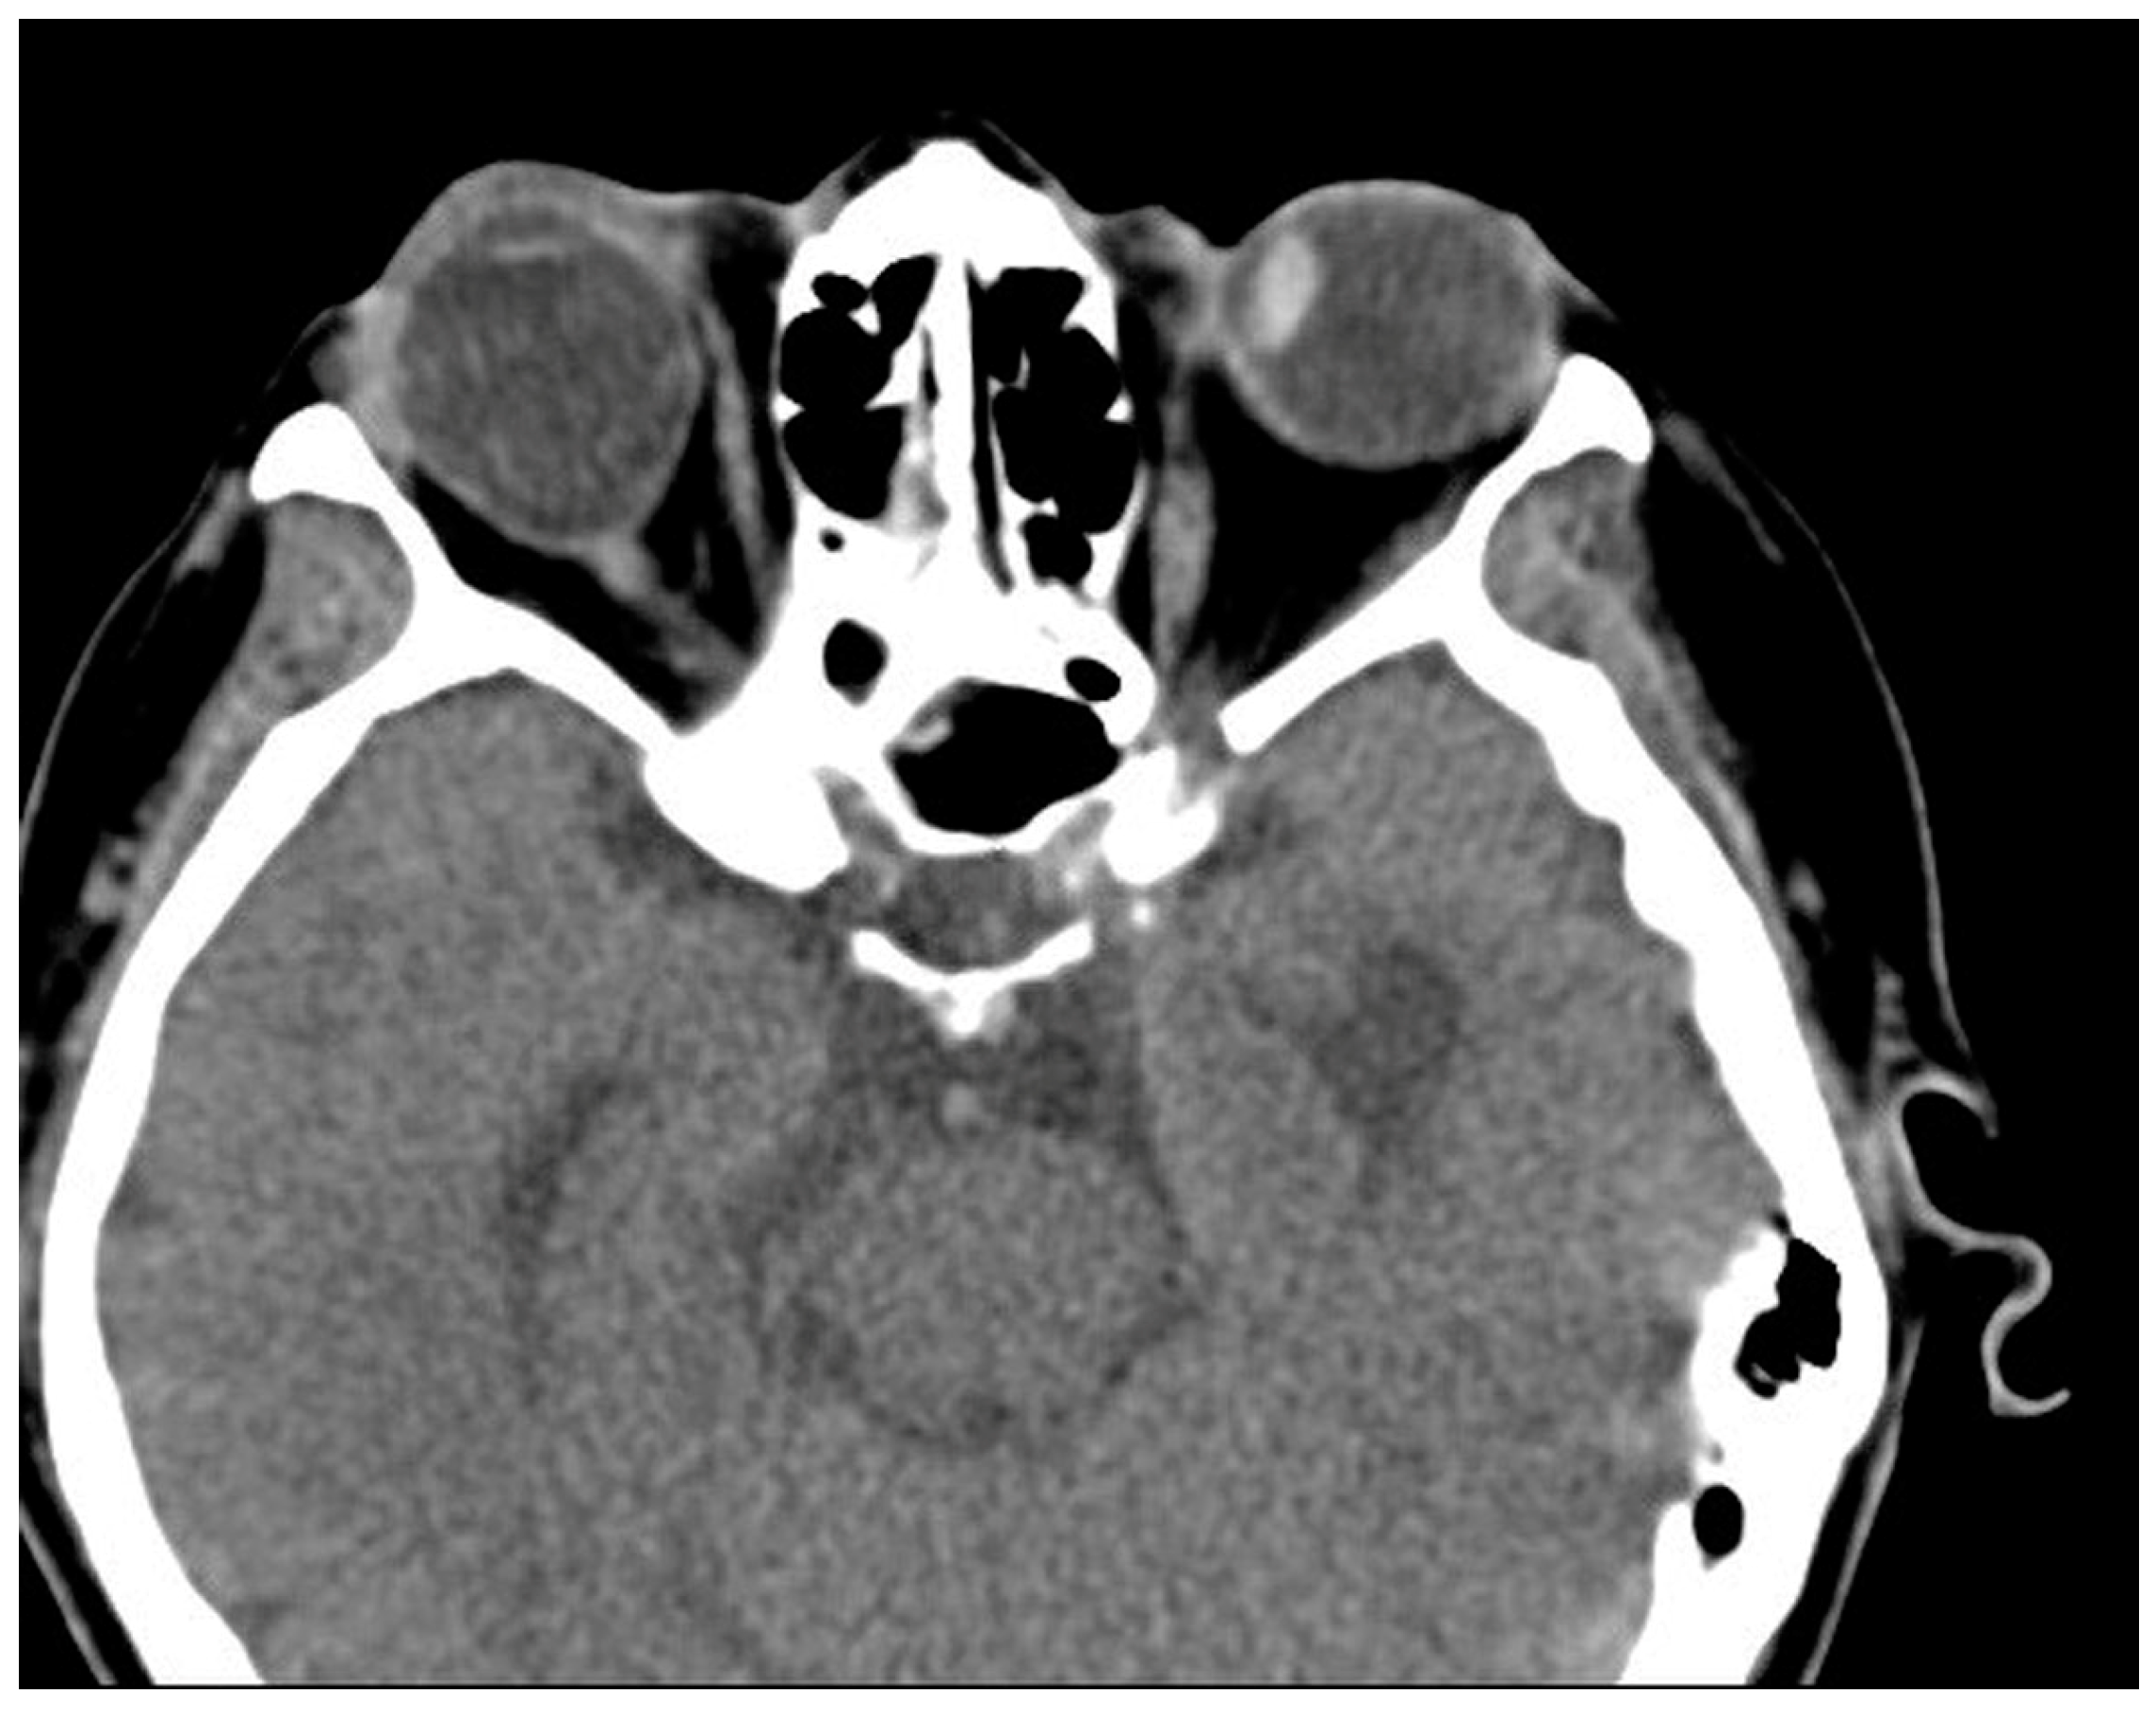

Case 2 was a 63-year-old male who presented with 100 PD ET in the right eye (Figure 1). His visual acuity was 20/200 in the right eye (SE, −0.5 D) and 20/20 in the left eye (SE, +0.5 D). Severe abduction deficit (−4) of the right eye was observed. Ten years before, the patient experienced a severe automobile accident. Optic atrophy of the right eye due to the traumatic optic neuropathy was observed during the fundus examination. Severe abduction deficit (−4) of the right eye was observed due to the sixth cranial nerve palsy that resulted from previous head trauma during the automobile accident. During strabismus surgery, severe restriction of the right MR by the forced duction test was noted, and the right MR was unintentionally disinserted during the procedure. After MR disinsertion, his esodeviation decreased from 100 PD to 30 PD and there was no restriction of the right MR. After two months, an additional right LR with a 7.0 mm resection was performed in the right eye. Two years after surgery, his esodeviation was 10 PD in the primary position of gaze without limitation in abduction or with little limited adduction (−1).

Figure 4. Postoperative CT image of Case 4. No definite abnormality is noted after left medial rectus muscle disinsertion.